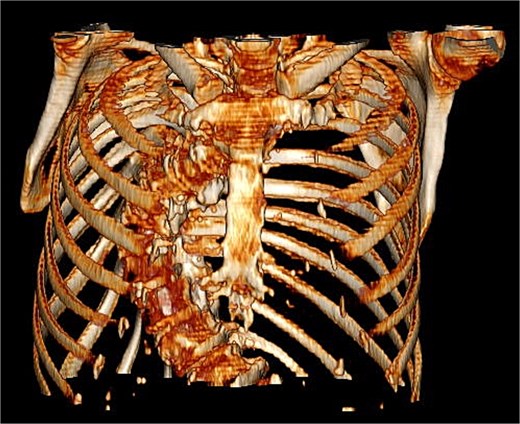

The patient’s comorbidities were extensive and included: heart failure with preserved ejection fraction (HFpEF), atrial fibrillation, left atrial enlargement, Barrett’s esophagus, hypertension, hypercholesterolemia, multiple benign hepatic cysts, osteoporosis, a large sliding hiatal hernia containing the gastric fundus and celiac artery, and descending thoracic aortic tortuosity causing chronic left lower lobe segmental atelectasis (Fig. 2).

Coronal CT showing curvature of the thoracic aorta tortuosity compressing the distal esophagus and causing chronic left lower lobe segmental atelectasis.